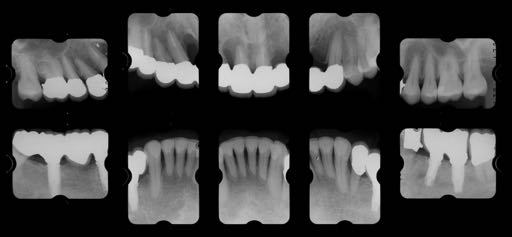

治療前

Zero Base Conceptsに基づく診断上の難易度

Degree of Difficulty +++

非常に治療難易度の高いケースである